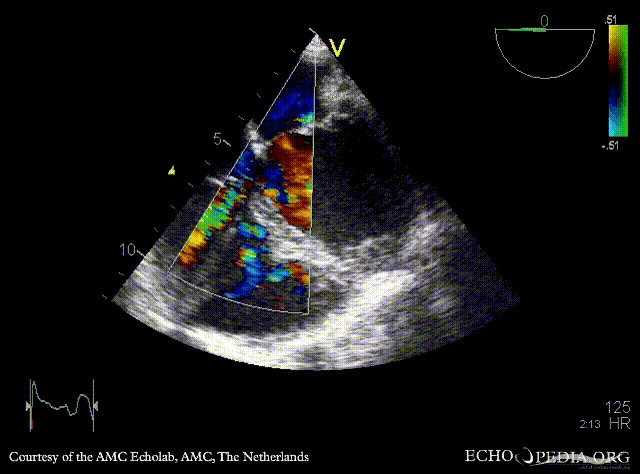

| A5CH: muscular VSD